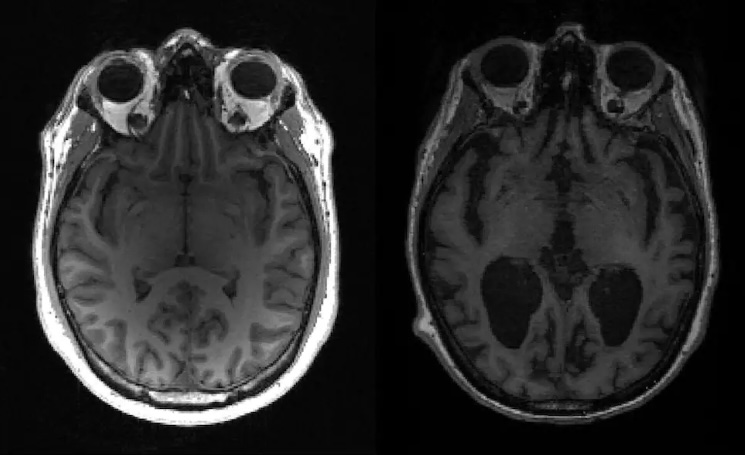

Currently, brain scans like PET (Positron Emission Tomography) are the most precise diagnostic tools we have, but they are expensive and scarce, with only a very small percentage of dementia-diagnosed patients accessing them woldwide. Even Magnetic Resonance Imaging (MRIs) are not always helpful in early stages. This is where AI comes in. It’s learned from thousands of pieces of patient data and can identify patterns that indicate potential disease. You don’t necessarily need any kind of invasive brain data. There are already large cohorts looking at electronic health records and school records right from infancy.

Our AI models are multi-modal, integrating various data types, including MRIs, cognition, genetics and biomarkers to provide a holistic analysis. Personally, I think the real revolution is going to come from digital data.